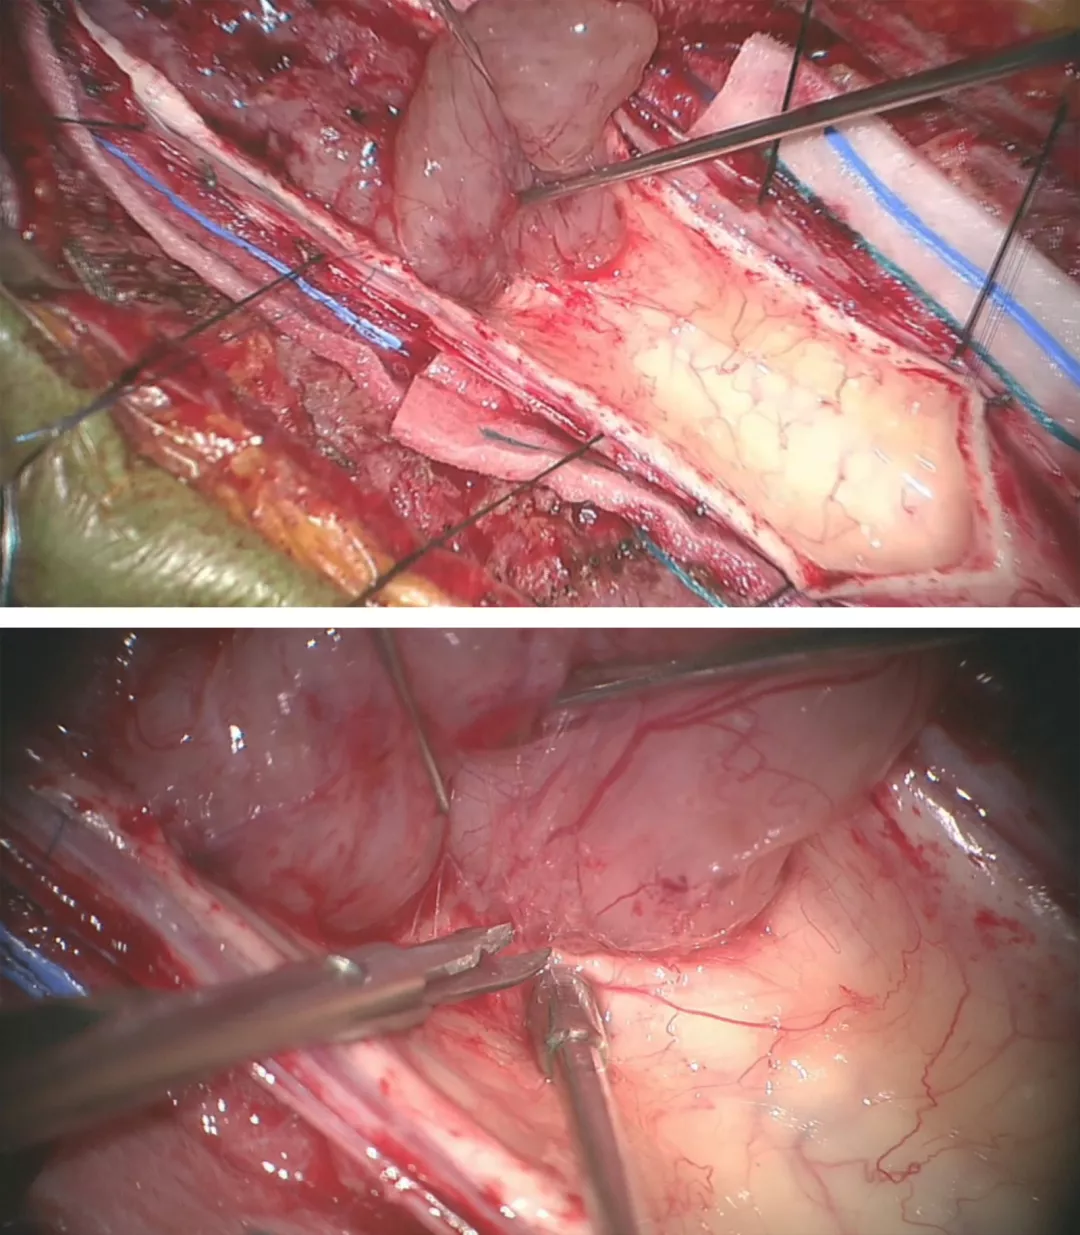

图7:采用娴熟的显微操作技术将瘤壁自菲薄的脊髓上剥离下来。由于肿瘤出血或空洞导致脊髓与肿瘤之间形成一个明显界面。大多数室管膜瘤和脊髓之间存在明显的肿瘤-脊髓界面。一般室管膜瘤的前方均有自脊髓前动脉发出的小动脉供血。在切除肿瘤时,这些肿瘤穿支血管要仔细分离、予以电凝后切断。盲目地牵拉会导致这些血管的撕裂,从而在止血过程中可能导致临近血管和脊髓的损伤。

笔者在切除髓内肿瘤过程中遵循一些原则。在切除肿瘤过程中尽量牵拉肿瘤壁而非脊髓来暴露界面和视野。视野干净有利于保持分离界面清晰。先采用超声刀进行肿瘤减压以便于牵拉肿瘤过程中不造成脊髓损伤。

笔者不建议强行剥离室管膜瘤的囊壁,因为目前研究表明这些囊壁不含肿瘤细胞,但这一操作却会很有可能导致脊髓损伤。

图8:血管母细胞瘤是高度富含血供的肿瘤,同时由于其组织来源为软膜血管周围间叶组织而非间质组织,因而其分离应该限于软膜而尽量避免脊髓组织损伤。鉴于其血供丰富且边界清楚,血管母细胞瘤的切除最好采用整块切除。血管母细胞瘤通常位于后外侧沟(背根入口区)。这一类似血管畸形的瘤体在分离时应仔细对瘤体进行去血供。在切除过程中,可采用小功率双极进行电凝以缩小瘤体体积从而使其界面更加清楚,易于分离。血管母细胞瘤的囊性部分或空洞可使分离更加容易。在瘤体深部与脊髓之间由于反复的小出血或压迫会造成肿瘤瘤体与脊髓也有一层界面。

切除髓内血管母细胞瘤主要包含以下几个要点:1)蛛网膜和神经根的分离、小功率双极电凝瘤体表面以及瘤体与脊髓界面的识别与分离;2)软脊膜及脊髓的切开及肿瘤的暴露,尤其是体积巨大的肿瘤;3)在处理体积较大的血管母细胞瘤时,采用6-0 prolene缝线适当牵拉软脊膜以暴露瘤体,电凝供血动脉,最后完成瘤体分离后再切断引流静脉,最终切除肿瘤。